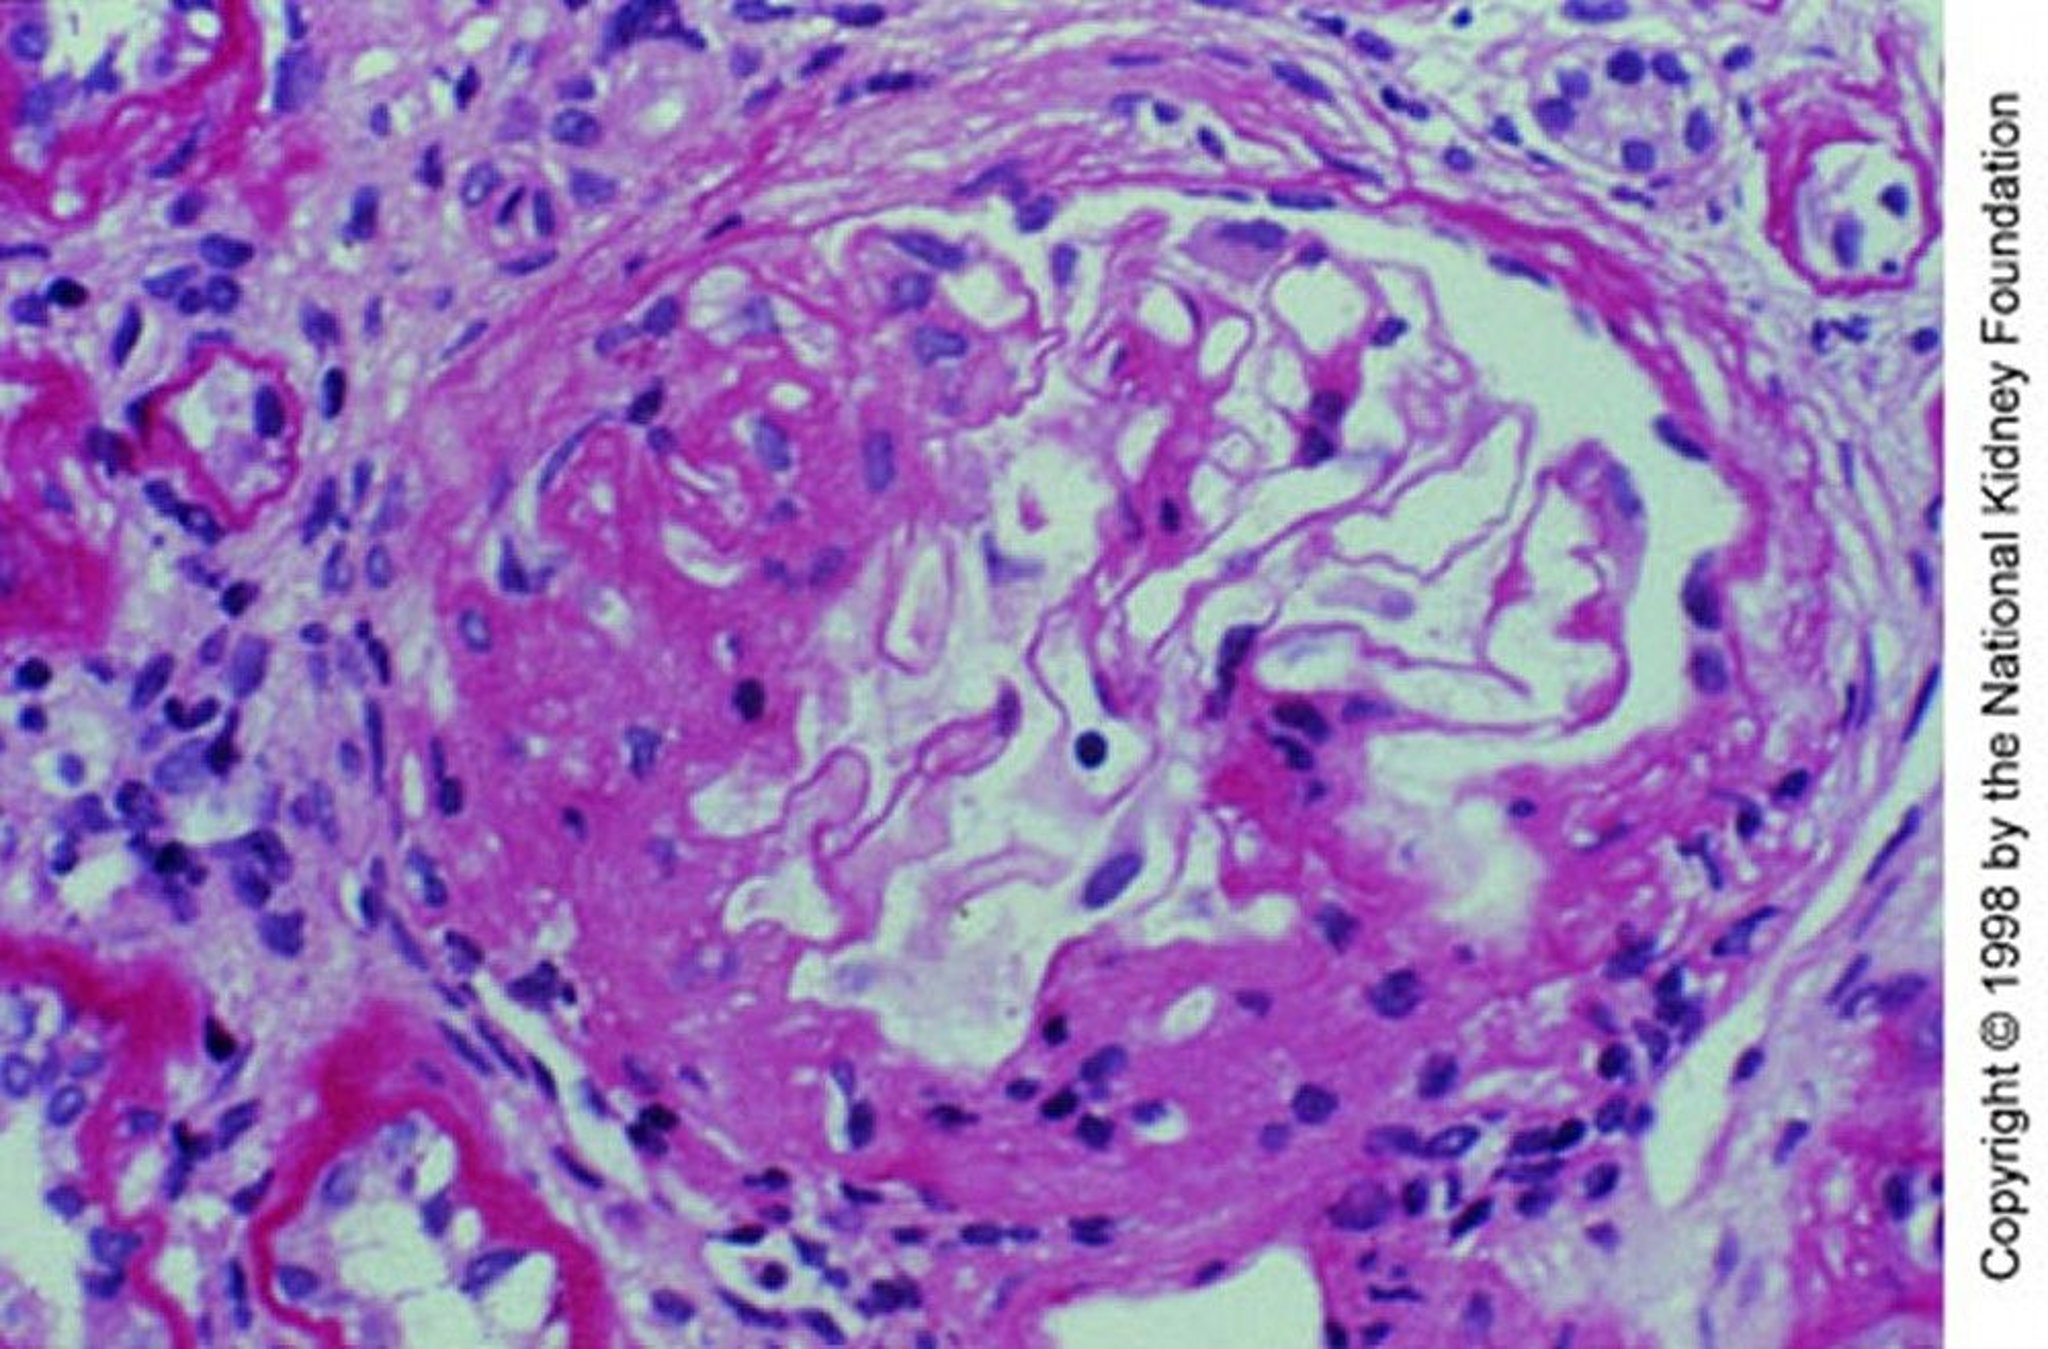

IgA Nephropathy (Mesangial Expansion)

Mesangial expansion with segmental sclerosis (periodic acid-Schiff stain, ×200).

Image provided by Agnes Fogo, MD, and the American Journal of Kidney Diseases' Atlas of Renal Pathology (see www.ajkd.org).